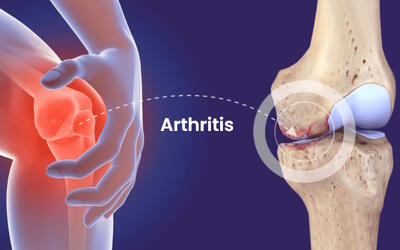

با آرتروز بیشتر آشنا شوید + فیلم

آرتروز یکی از بیماریهایی است که مفاصل را درگیر میکند.

بهترین ورزش ها برای آرتروز و مشکلات ستون و فقرات

آرتروز و مشکلات ستون فقرات از جمله بیماری های مزمن دستگاه اسکلتی-عضلانی هستند که به دلیل تغییرات دژنراتیو در مفاصل، مهره ها و دیسک های بین مهره ای بروز می